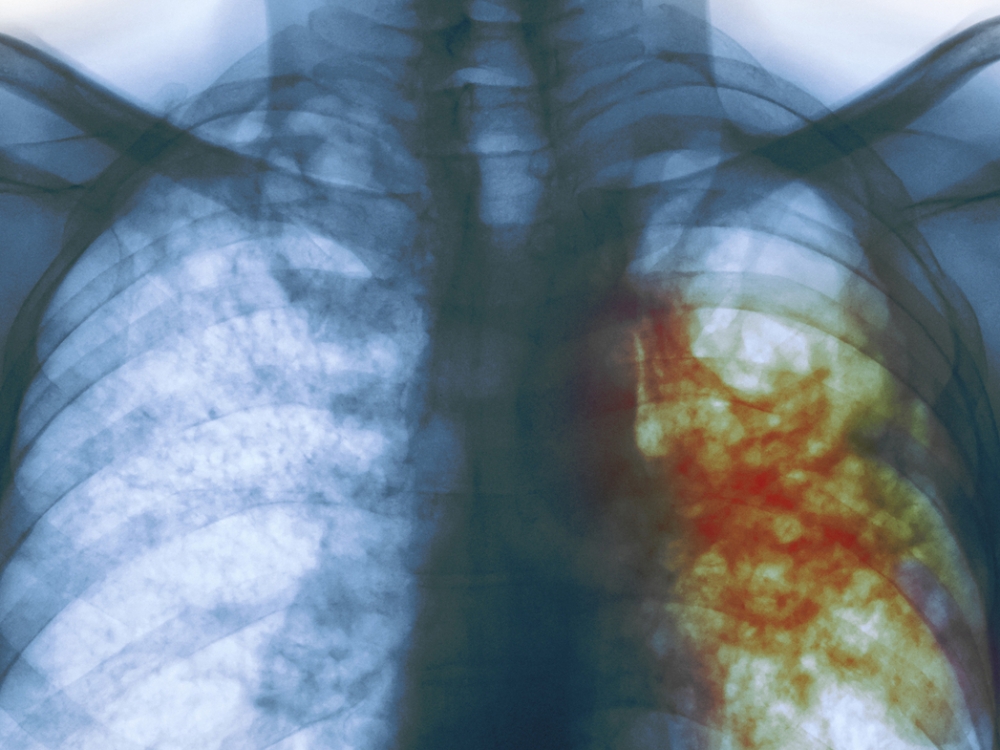

Šiuo metu Alytaus apskrities tuberkuliozės ligoninėje sergantiems tuberkulioze yra skirta 60 lovų. R. Radivono pateiktais duomenimis, iš ligoninėje besigydančių net 90 proc. pacientų serga atvira, 50 proc. – vaistams atsparia tuberkuliozės formomis. Jeigu šia liga sergantys asmenys vengia gydytis patys, nevartoja gydytojų paskirtų vaistų, nepasirenka jiems tinkamo gyvenimo būdo, jie būna gydomi ir priverstinai.

Sveikatos apsaugos ministerijos (SAM) duomenimis, susirgimų tuberkulioze Lietuvoje nuo 1998 m. sumažėjo du kartus, tačiau kai kurių ligoninių, kuriose gydomi šia liga sergantys pacientai, atstovai išreiškė susirūpinimą, kad situacija nėra gera. Pasirodo, tarp Europos Sąjungos (ES) šalių esame antrieji (pirmauja Rumunija), nes mūsų šalyje sergamumas tuberkulioze yra tris kartus didesnis nei ES vidurkis.

Susirgimų tuberkulioze Lietuvoje statistika iš tiesų liudija, kad sergamumas tuberkulioze yra sumažėjęs: jeigu 1998 m. šia liga sergančių Lietuvoje buvo 3 tūkst. 200, tai 2021 m. – 646, tačiau 2022 m. šis skaičius ir vėl šiek tiek padidėjo – buvo 738 pacientai, o 2023 m. – 723 sergantieji.